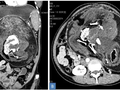

Hình ảnh CT scan trường hợp "thai nhi trong bào thai" được phát hiện bên trong bụng của một người phụ nữ Ấn Độ. Ảnh: Gizmodo

Trường hợp hy hữu trong y học: Người phụ nữ “mang thai” suốt 17 năm mà không hề hay biết